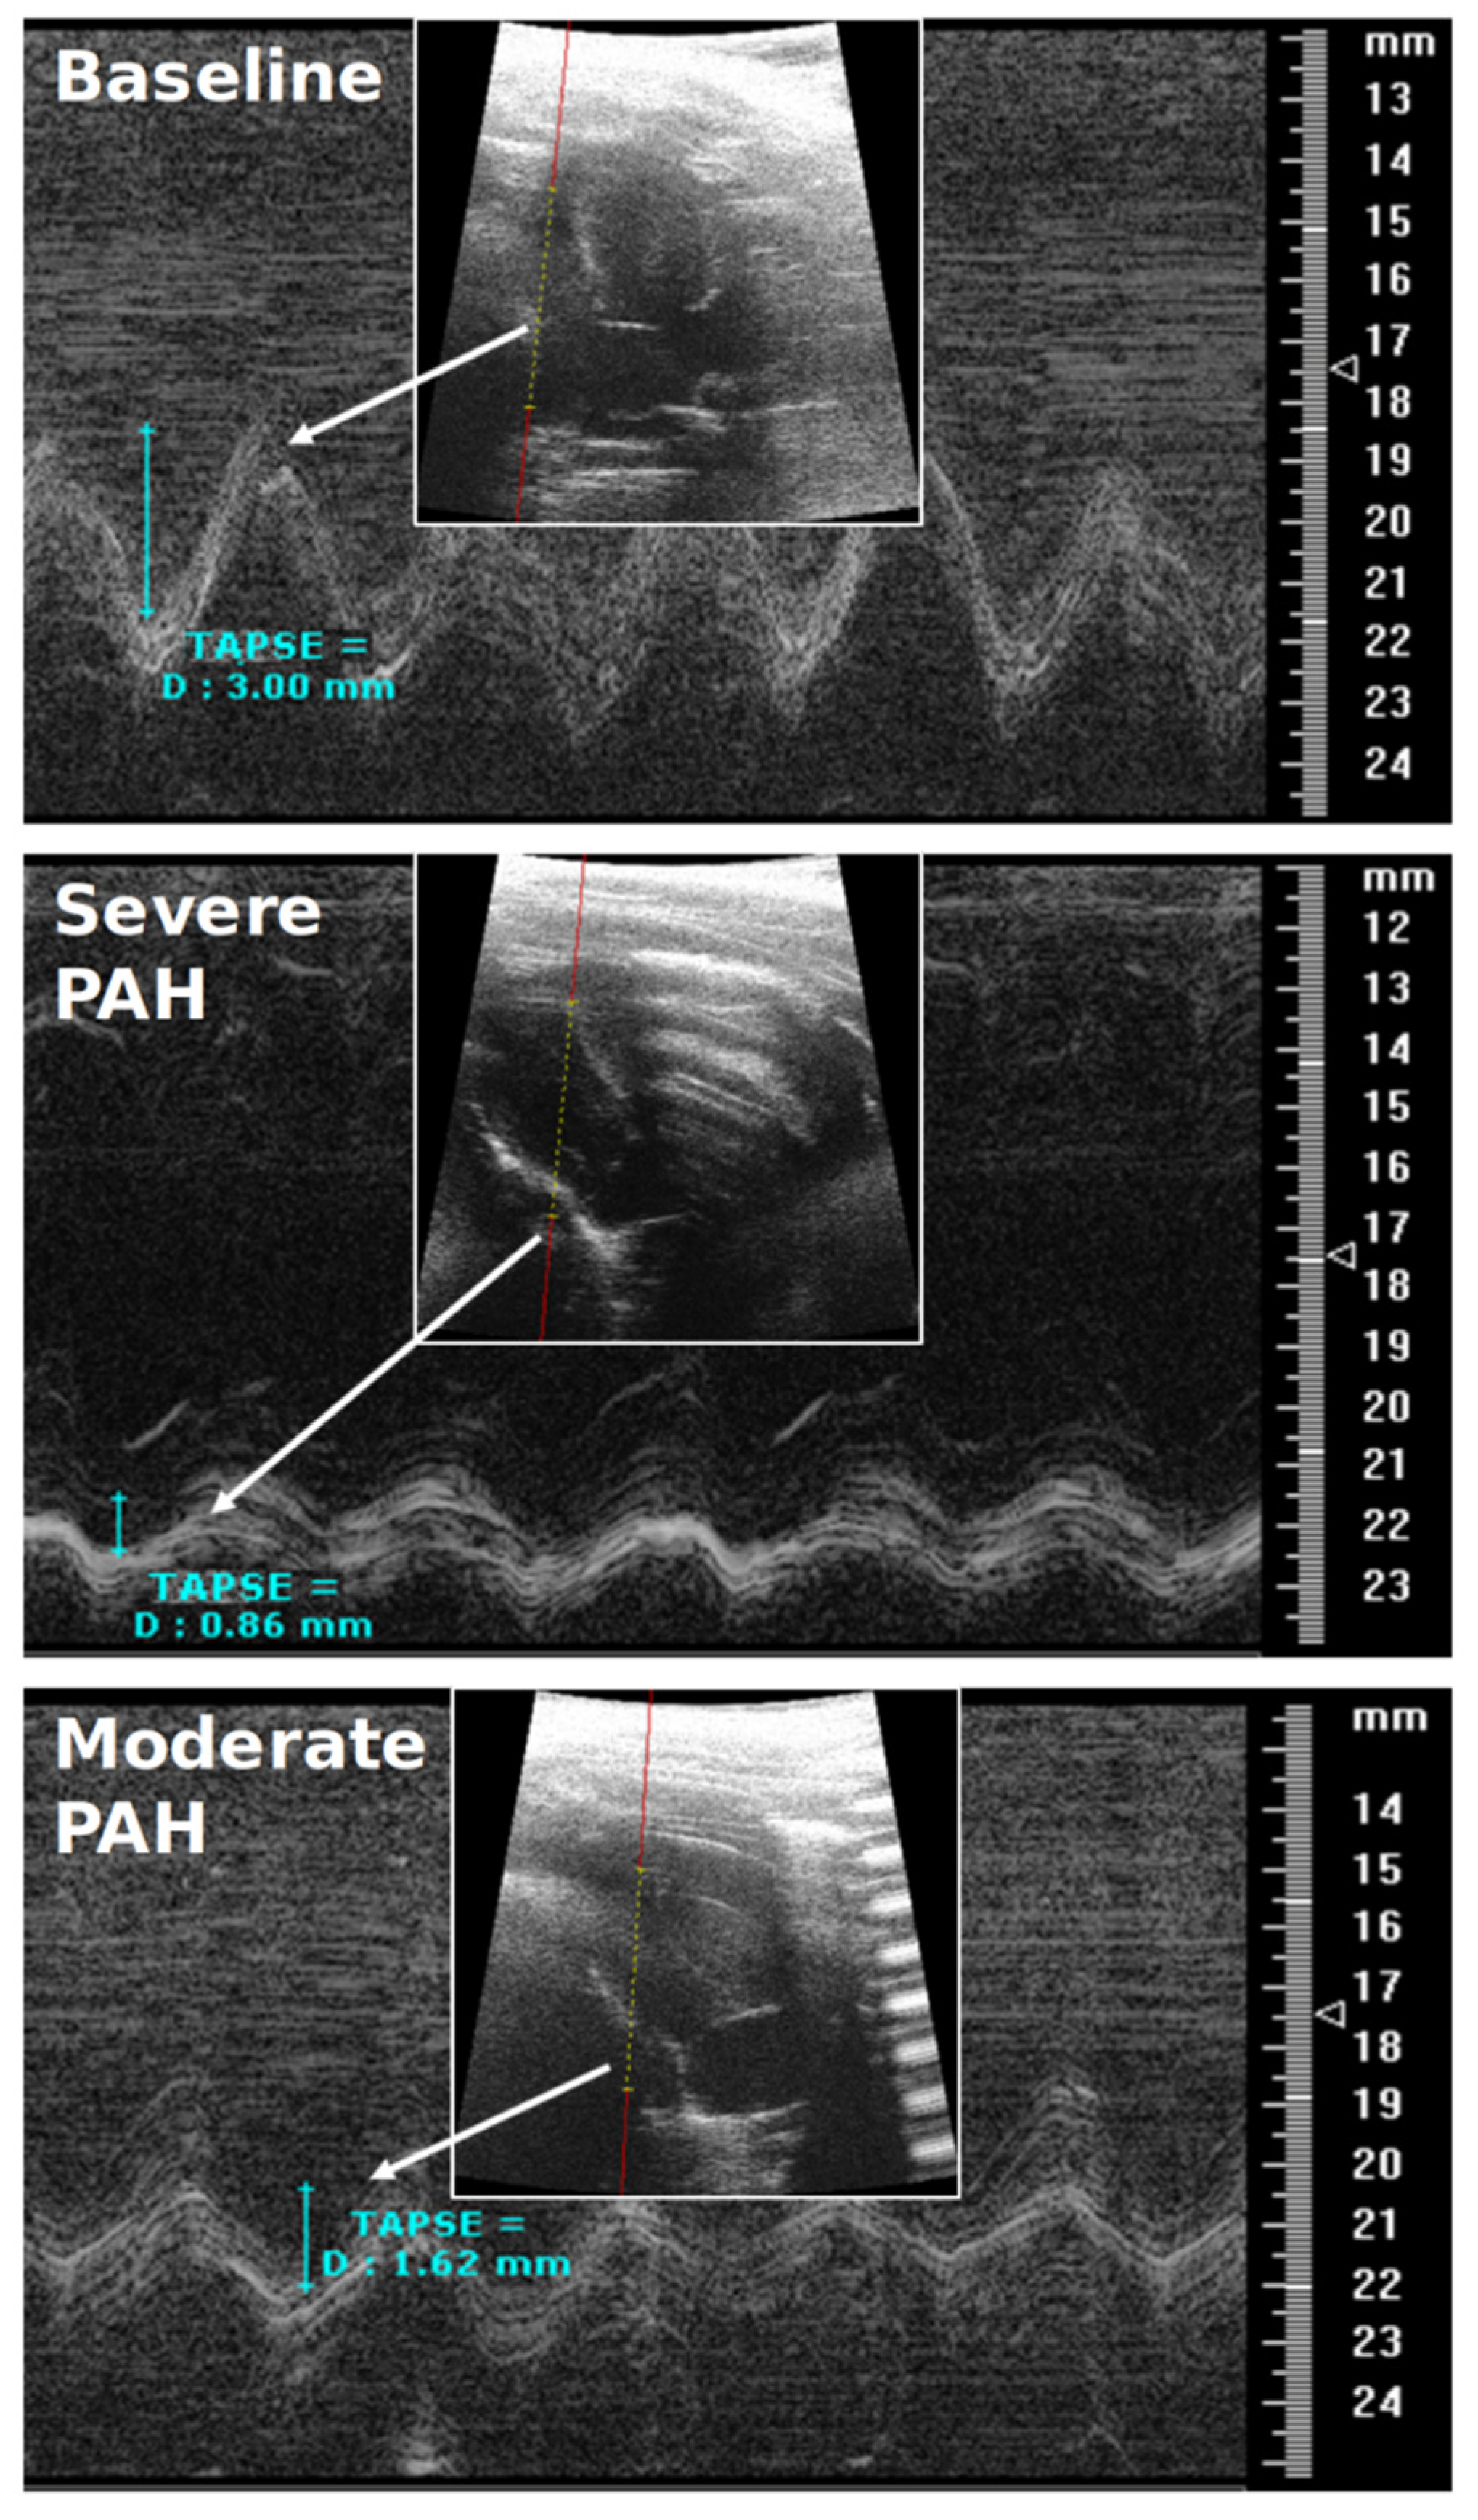

- RVEF & TAPSE: Due to the pitfalls and difficult procedure of RHC in rats, RVEF and TAPSE were investigated by CMR and TTE to prove all the animals were influenced by PAH. RVEF could reliably differentiate all the experimental groups from each other (p < 0.05), i.e., it was largely reduced in severe PAH and preserved in the moderate stage (Table 2). TAPSE could also differentiate well between baseline and severe PAH as well as between the severe and moderate disease groups (p < 0.05) (Table 2) (Figure 4). The RVEF and TAPSE results proved the effectiveness of the experimental design.

| TTE: Tricuspid annular plane systolic excursion | TAPSE | mm | 1, 2 | 2.73 ± 0.64 | 1.03 ±0.17 | 1.27 ± 0.45 |